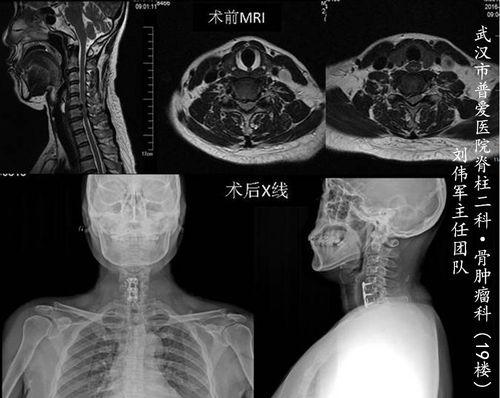

为了让大家更直观地了解颈椎前路手术的过程,我们找到了一段手术视频。下面,就让我们一起走进手术室,见证这一神奇的医疗过程。

手术前,医生会对患者进行详细的检查,确保手术的安全性。同时,患者也会接受一系列的术前准备,如禁食、备皮等。

医生会逐层切开皮肤、肌肉等组织,直到暴露出颈椎。在这个过程中,医生会仔细观察颈椎的情况,确定手术方案。